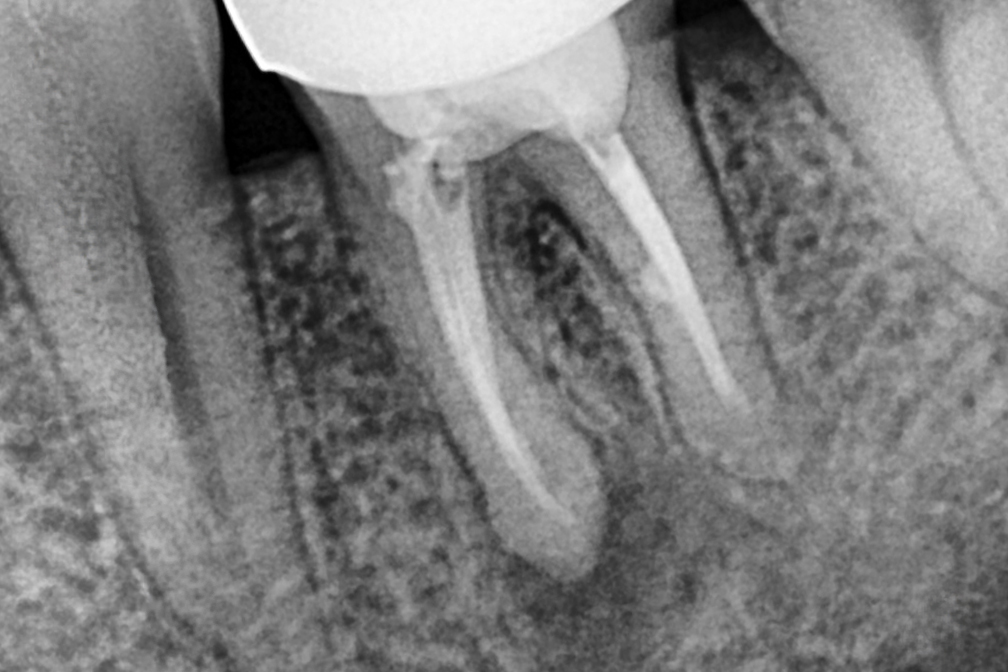

Before 2025년 6월 7일